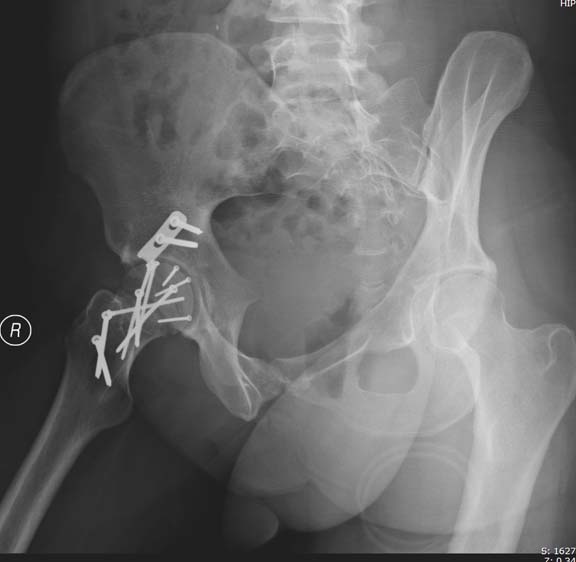

Здесь клинические примеры: Первый случай передний доступ, второй с ICP

monitor Flipp Trochanteris

и с переломом заднего края.